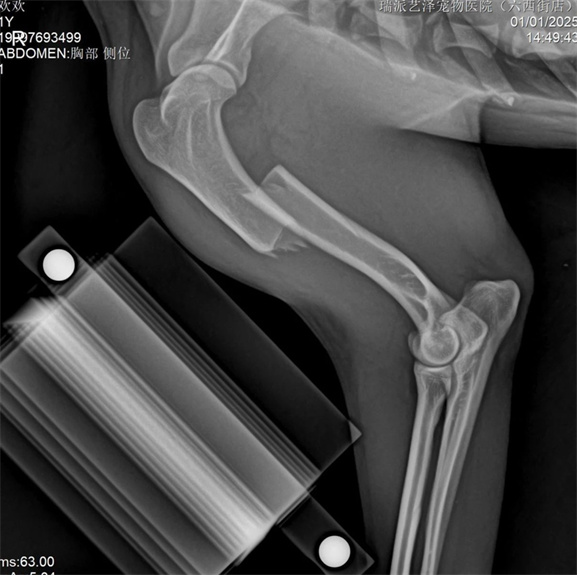

動物基本資料:鄉村犬,7公斤1歲,骨折原因:車禍

右脛骨幹粉碎性骨折(閉合性)

脛骨採用內側MIPO手術入路,盡可能保護軟組織,並以髓內釘及橋接骨板固定。

脛骨採用PRCL8mm接骨板和2.5mm穿刺針,確保近端和遠端至少有兩枚螺絲